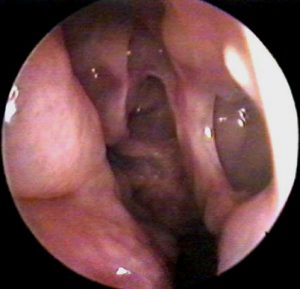

Vai trò của acid transamic trong phẫu thuật nội soi xoang – một tổng quan hệ thống và phân tích tổng hợp

Rhinology. 2013 Dec;51(4):291-7. doi: 10.4193/Rhin13.042. Role of tranexamic acid in endoscopic sinus surgery - a systematic [...]